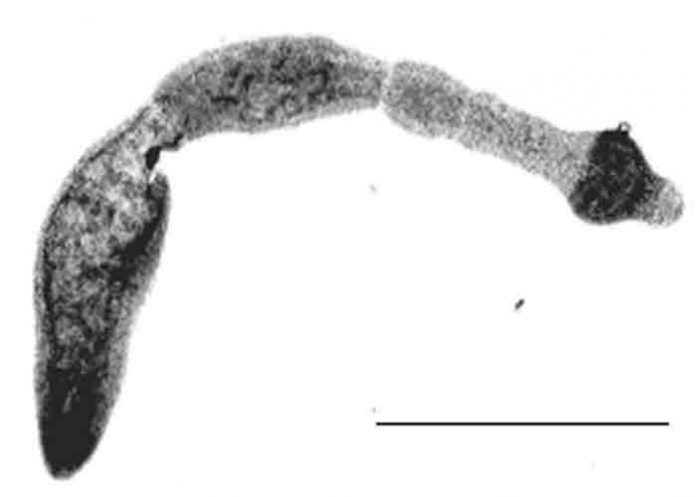

Se trata de una enfermedad rara y potencialmente mortal provocada por un parásito ‘importado’ de Europa que crece en el hígado; causando graves complicaciones de salud y hasta la muerte, según un comunicado emitido por la Universidad de Alberta.

La enfermedad se contrae al consumir huevos microscópicos de tenia al comer alimentos contaminados o al manipular animales infectados. Estos huevos pueden implantarse dentro de los órganos y desarrollarse en ellos.

Los huéspedes de este parásito son caninos, típicamente zorros y coyotes, pero potencialmente también en perros domésticos, aunque el parásito se considera relativamente inofensivo para ellos.

Cuando un roedor ingiere huevos de parásitos de las heces caninas, adquiere una forma diferente de la enfermedad y desarrolla un tumor, o crecimiento parasitario, en el hígado, que lo mata. Cuando un canino se come al roedor, el parásito vuelve a tomar la forma de tenia.